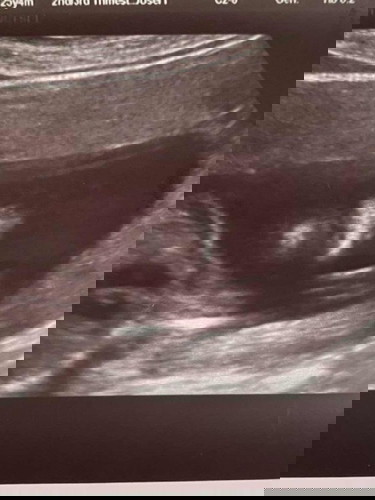

20 weeks ultrasound

Hi mommy! Pasagot naman po kung ano po yung nasa ibaba ng ilong ng anak ko? Kasi sabi butas daw po ng ilong yan. Parang may hiwa sa ilalim ng ilong. Wala naman po sinabi sakin yung nag ultrasound sakin. Kinakabahan kasi ako na napapraning kung ano yung medyo hiwa or di lang maayos pagka print. Di ko po alam e 🥺